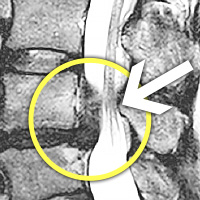

MRI

㸮 , Ͽ Ͽϴ.

㸮 , , ٷ Ͽ Ͽϴ.